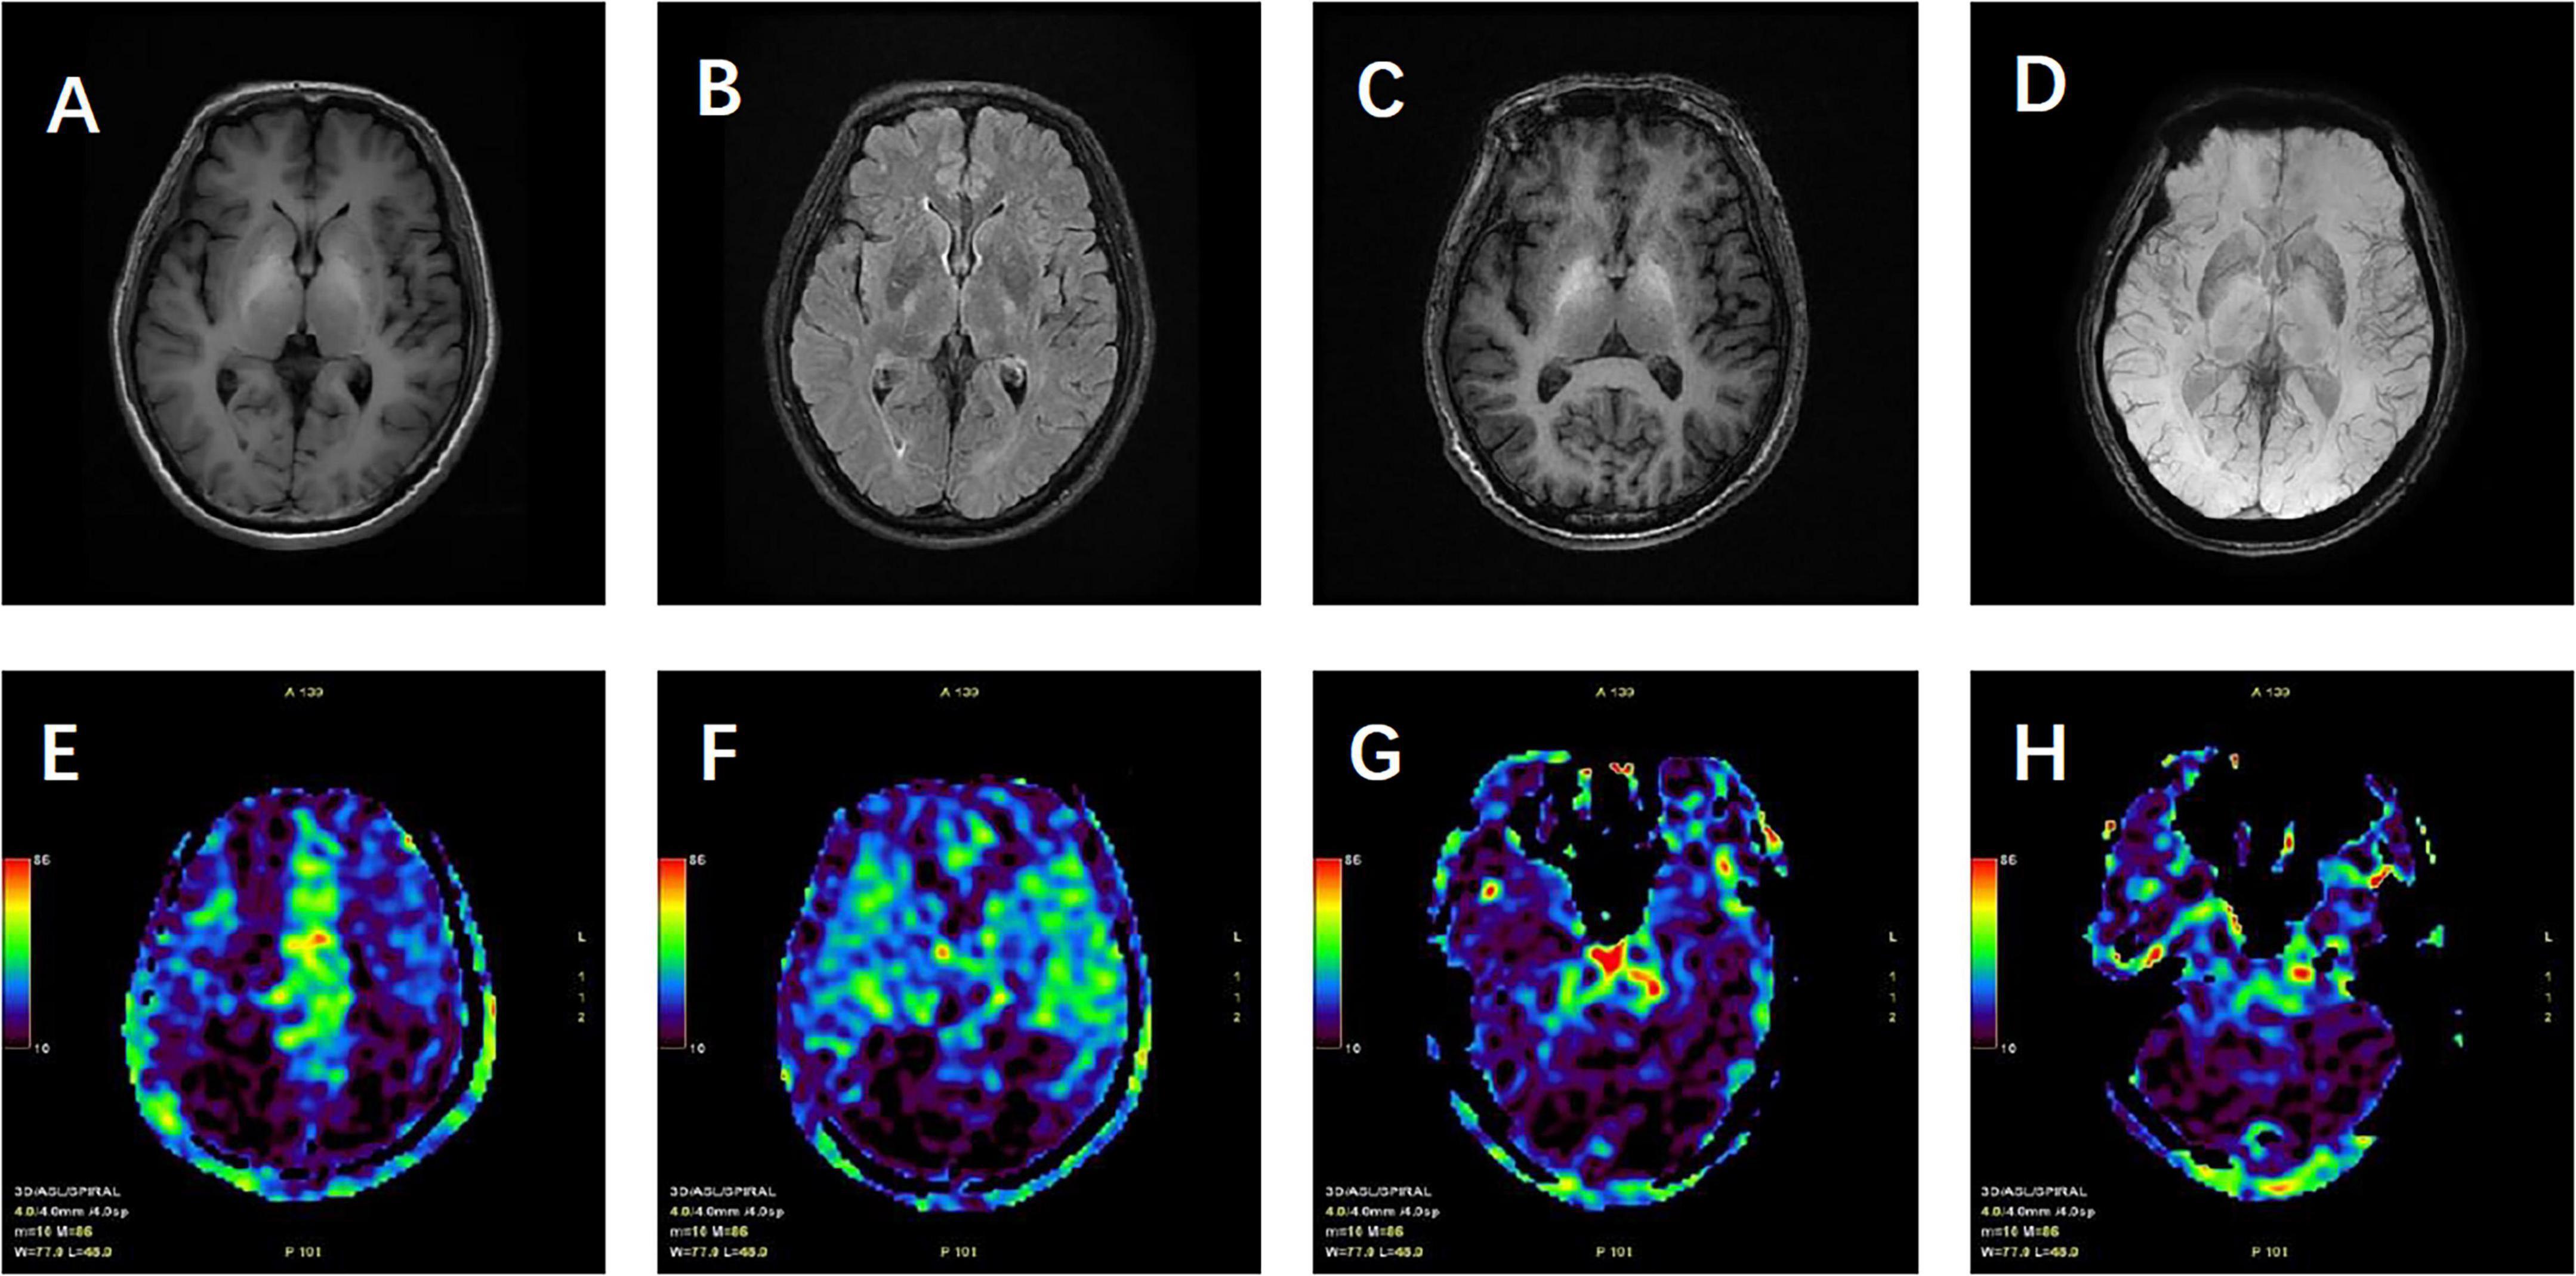

[Abstract] This case report examines the diagnostic and therapeutic complexities presented by a patient with hepatic encephalopathy resulting from overlapping pathologies of non-alcoholic steatohepatitis (NASH), hepatitis B virus (HBV) infection, and non-cirrhotic portal hypertension (NCPH). Highlighting the intricate relationship among these conditions, this study delineates the distinct and overlapping clinical features, diagnostic challenges, and therapeutic approaches. The patient exhibited atypical symptoms typical of NASH but lacked clear signs of cirrhosis, complicating both the diagnostic process and the therapeutic management. The diagnostic journey involved a nuanced assessment using multimodal imaging techniques, which were crucial in distinguishing between hepatic encephalopathy caused by cirrhosis and that due to NCPH. Treatment strategies had to be carefully tailored to address the specific etiological factors and pathology of the conditions involved, with particular attention to managing metabolic disorders such as insulin resistance and abnormalities in lipid and glucose metabolism, frequently observed in both NASH and HBV. The case underscores the need for a comprehensive and individualized approach in managing complex hepatic conditions, especially when conventional diagnostic criteria and treatment protocols face limitations.